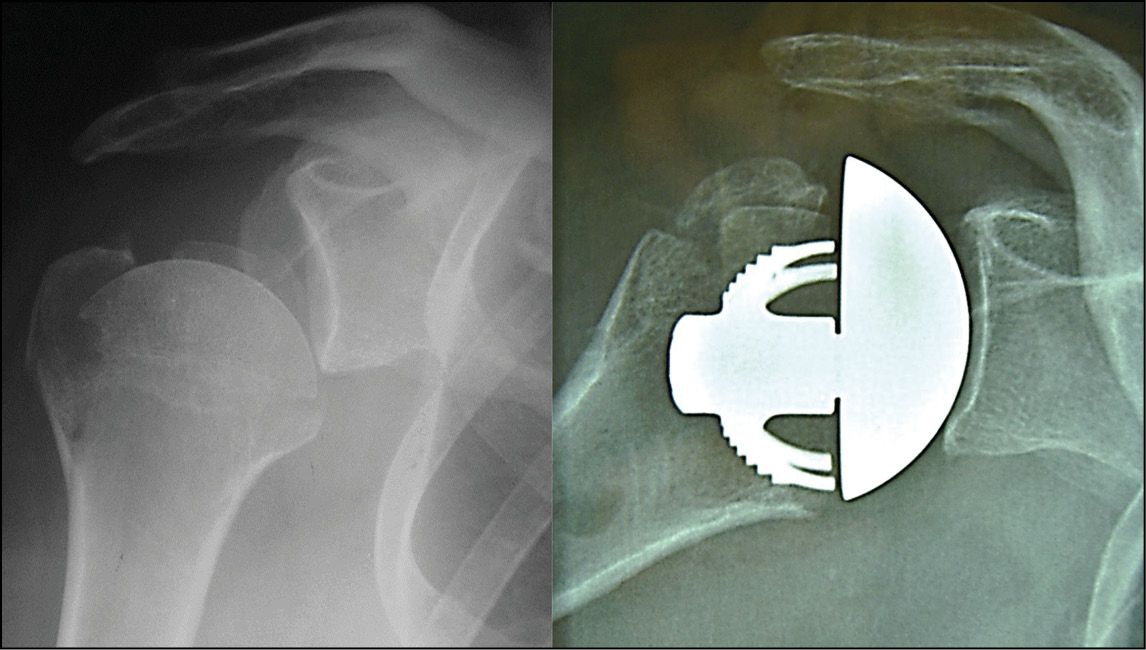

Post-instability osteoarthritis, which usually occurs in relatively young subjects with good quality bone, is a good indication for a minimally-invasive anatomical TSA. A universal metaglene component should be recommended so that it can be converted to a reverse implant, should the instability recur or should there be loosening of subscapularis weakened by a previous bone block (Fig. 13).